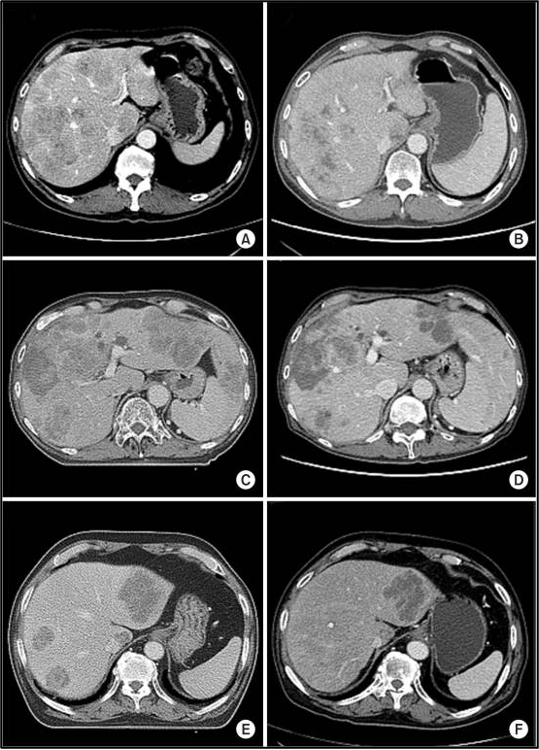

מתוך 10 המטופלים שקיבלו טיפול קרינתי לכל הכבד (WLI) עם היפרתרמיה, מחלה פרוגרסיבית (PD) של גרורות בכבד נצפתה בשני מטופלים (20%), ושלושה הציגו תגובה חלקית (PR) (איור 2). לאחר חודשיים, השלושה האחרים הציגו מחלה פרוגרסיבית (PD) בכבד, ושלושה נותרו ללא מחלה פרוגרסיבית (PD-free) 3 חודשים לאחר הטיפול.

להלן איור 2 : שינויים בתמונות ההדמיה של טומוגרפיה ממוחשבת (CT) לאחר טיפול קרינתי לכל הכבד (WLI) בשילוב עם היפרתרמיה: 3 מתוך 10 מטופלים הדגימו תגובה חלקית (partial response) חודש אחד אחרי הטיפול. תמונות הדמיית CT שנלקחו לפני (A,C,E) וחודש אחרי WLI (F,D,B)